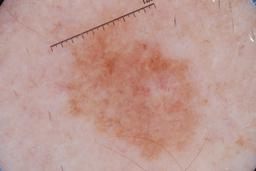

MSK-4

- Name: MSK-4

Description:

Images found based on a search for patients with a personal history, clinical diagnosis, or differential diagnosis of melanoma. All diagnoses confirmed by histopathology.